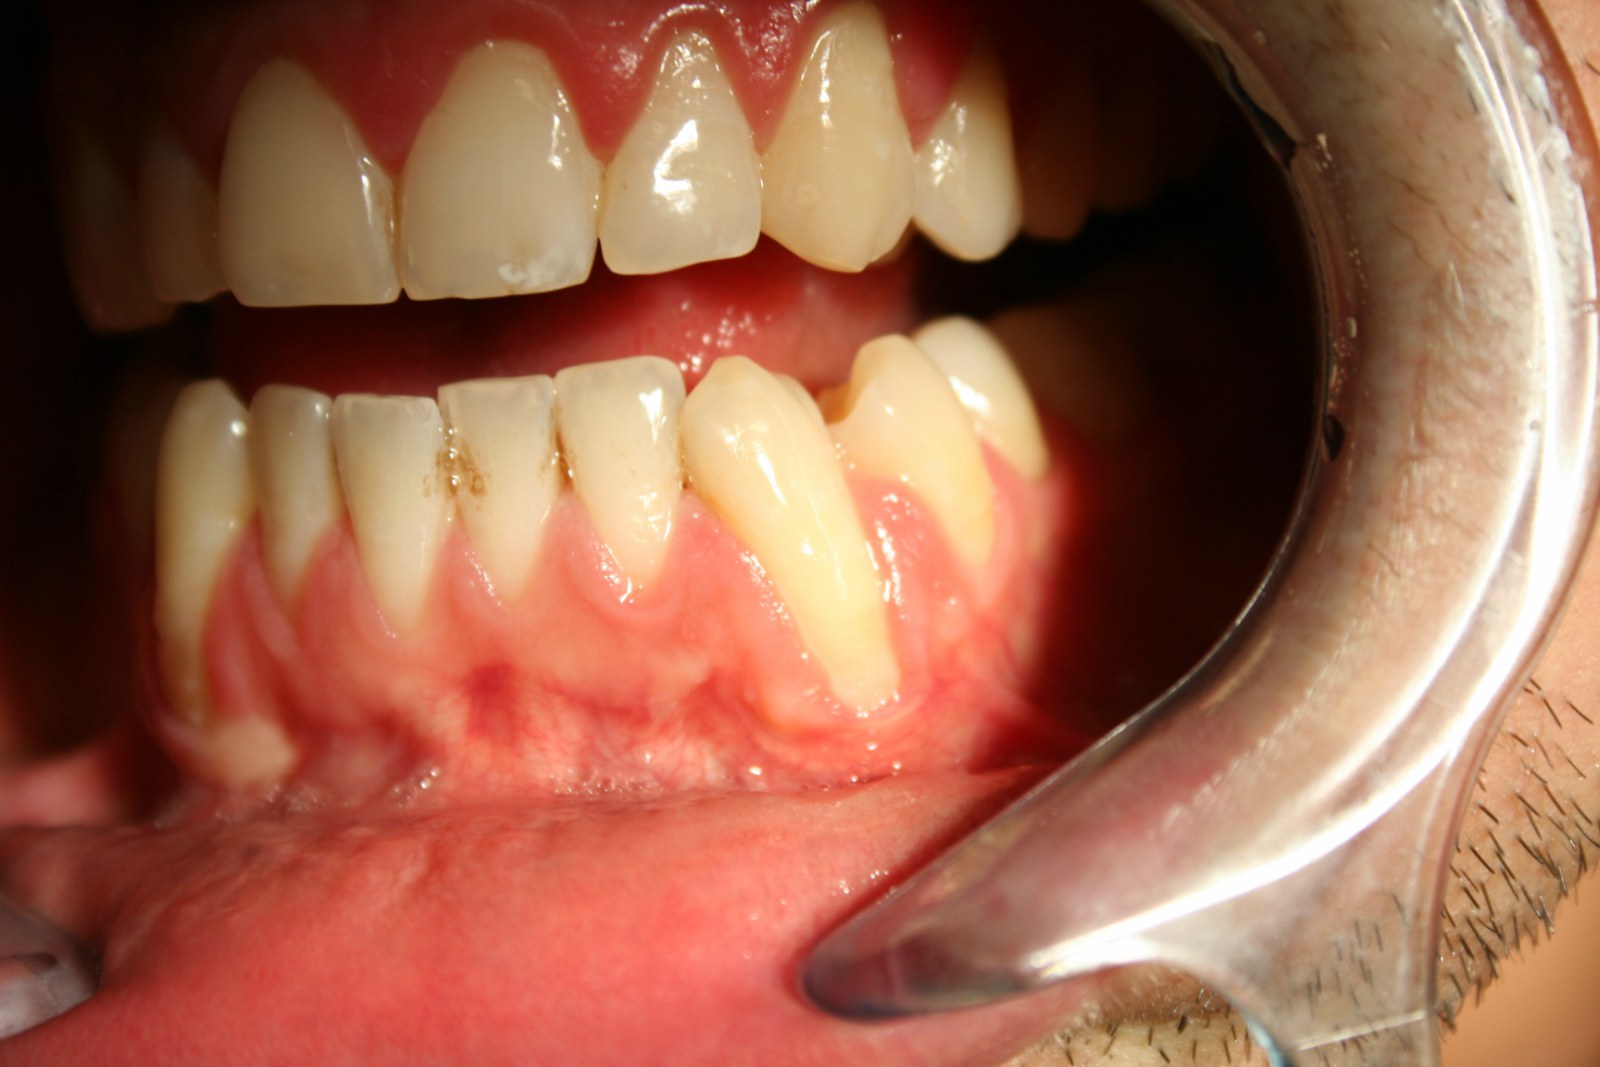

Intra Oral Plastic Dentistry (Gums)

Intraoral plastic surgery can reduce gum recession and bone loss, making your smile healthier while improving its appearance. In some cases, these treatments can cover exposed roots to protect them from decay. Whether you have intraoral plastic surgery to improve function or esthetics, patients often receive the benefits of both: a beautiful new smile and improved periodontal health – your keys to smiling, eating and speaking with comfort and confidence.

What Causes Uneven Gums?

A number of things can cause your gums to be too low or too high. Gums that cover a large portion of your teeth can make your teeth look small. This may be the result of genetics, a particular health problem, or taking certain prescription drugs. Gums that are too high and make your teeth appear long are often caused by gum recession, a condition in which gum tissue pulls back from a tooth and exposes the tooth's root. Not only can gum recession make your teeth look long, it can lead to serious dental problems such as decay and tooth loss. Gum recession may also be a sign of periodontal disease, the deterioration of the supporting structures of the teeth (gums and bone) . Cosmetic Dentistry: